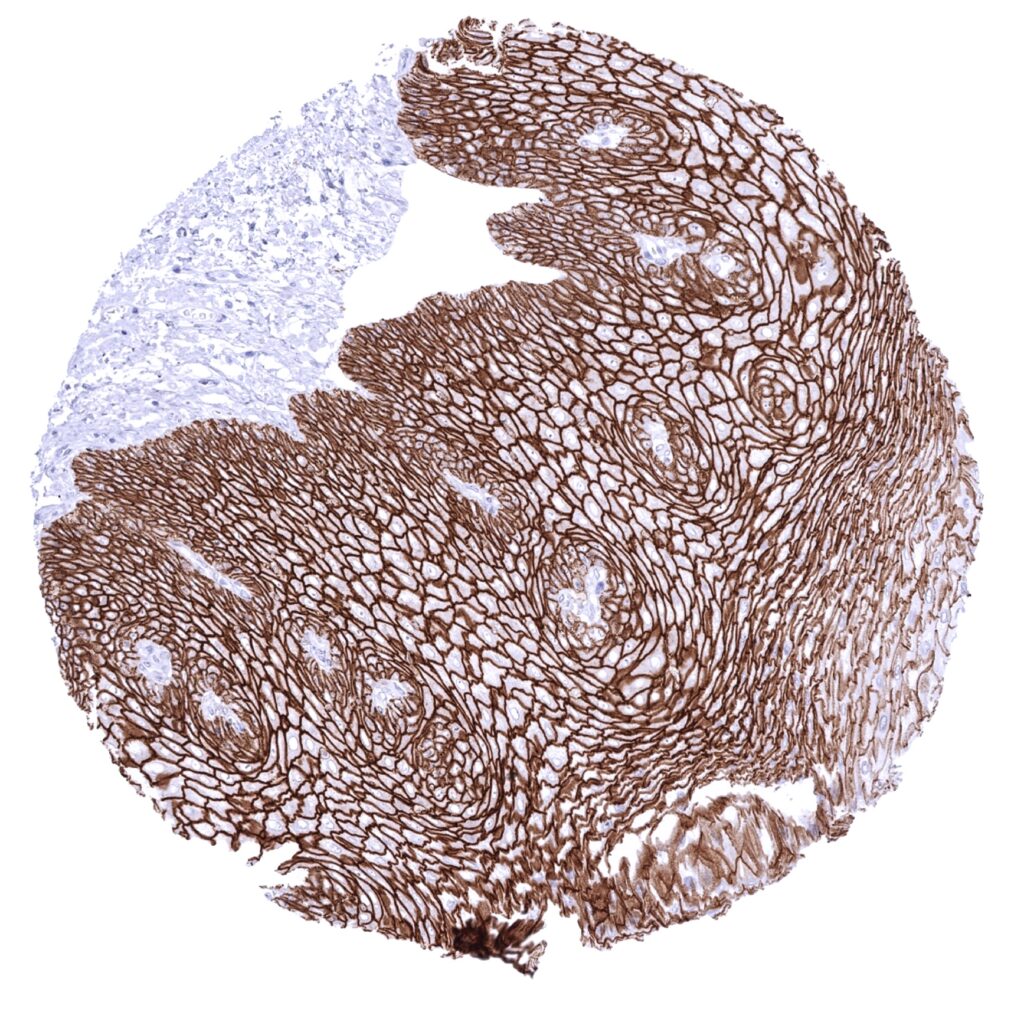

E-Cadherin antibody [MSVA-035R] HistoMAX

Urinary bladder, urothelium

Uterus, ectocervix